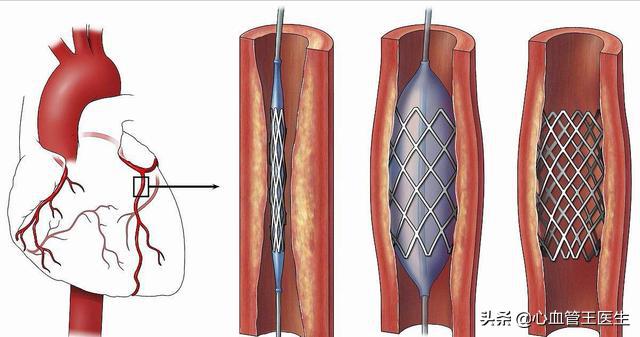

ステップ1、パンク。末梢動脈を見つけ、この動脈から穿刺を行うが、最も一般的な選択は、手の付け根か太ももの末梢動脈を選択することである。

ステップ2、チューブの挿入。その末梢血管開口部からシースを挿入し、適切なサイズのシースを選択してガイドワイヤーを進め、冠動脈開口部付近の心臓までゆっくりと送り込む。

ステップ3:軌道を確立する。最初のガイドワイヤーは冠動脈より太いので、この時は細いガイドワイヤーを選んで冠動脈病変の遠位部を通過させ、まずバルーンで拡張しなければならない。

ステップ4:ステントを留置する。バルーンの拡張が完了したら、このガイドワイヤーに従ってステントを留置する。

心臓ステント留置術は、閉塞した血管にステントを挿入し、閉塞を解除することで心筋への正常な血液と酸素の供給を回復させ、心臓の正常な機能を維持するインターベンショナル手技である。ステント留置術は心臓内で行われ、異物が挿入されるため、多くの患者さんがステント留置術の安全性を心配している。実際、過度の心配は不要である。

第二に、ステント留置術そのものについては、患者は過度に心配する必要はない。ステント留置術は大病の部類に入るが、それ自体は成熟した手段であり、腫瘍摘出や臓器移植などの他の手術に比べ、成功率が高く、安全性も確実である。ステント留置術は低侵襲手術であり、人体への外傷も少なく、また、循環器科の手術の中で最も一般的なものであることから、ステント留置術はすでに極めて成熟した手術であり、専門病院で専門医が行う限り、成功率は絶対的に保証される。ステント留置の心配については、実はその必要はない。現在、臨床で使用されているステントのほとんどは、コバルト、クロム、ニッケルなどの合金製で、組織適合性に優れ、拒絶反応やアレルギーのリスクはない。さらに、ステントは時間とともに血管壁に埋め込まれ、血管と一体化していくので、患者がステントの位置ずれやズレを心配する必要もない。したがって、手術もステント自体も比較的安全である。